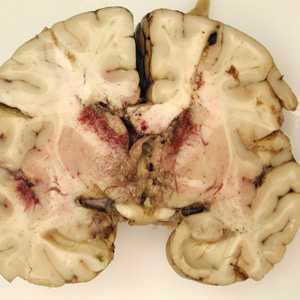

March - 2008 - Case #223

A seven-year-old, previously healthy child developed flu-like symptoms and rapidly progressive bulbar palsy, coma, and eventually death. Imaging revealed florid ventriculitis. A viral etiology was initially suspected.